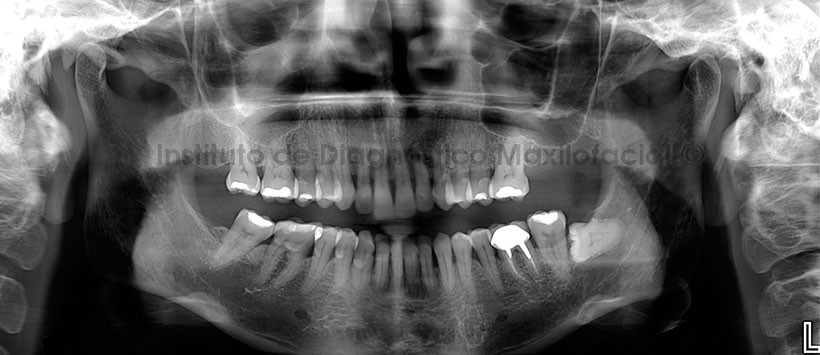

En la radiografía panorámica de control posqurirugica (ortopantomografía) se visualiza de manera parcial el cornete inferior de lado derecho, neumatizacion alveolar de ambos senos maxilares, ausencia de piezas dentarias, pieza 36 (material de obturación, espigo y corona protésica), pieza 38 impactada mesioangulada y la presencia de un diente supernumerario proyectado entre las porciones radiculares de las pieza 24 y 25. (Figura 2)